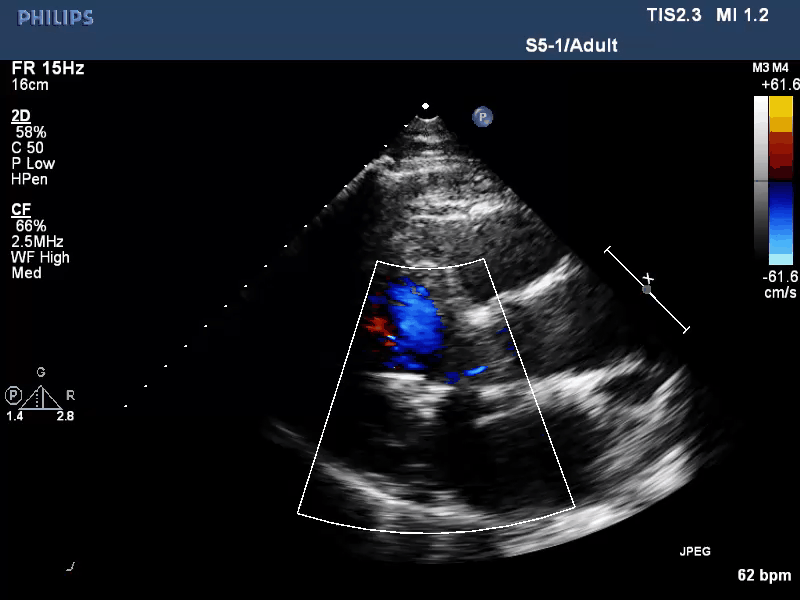

经食道超声心动图(TEE)提示:二尖瓣病变Carpentier II型,DMR,二尖瓣2区反流及P2腱索断裂并瓣叶脱垂,Gap 6 mm,Width 15 mm, 瓣口面积6.7 cm²,2区前叶长20 mm,后叶长19 mm。MR4+,反流束来自于2区,偏心性反流束,指向前叶;VC 11 mm。房间隔穿刺空间约4.5 cm。

术前TEE XPLANE

术前TEE XPLANE COLOR